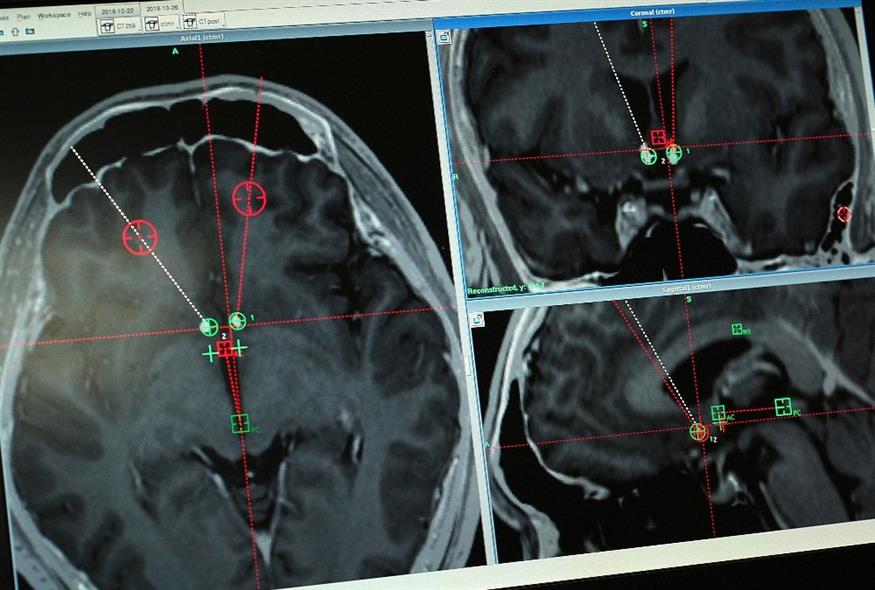

Καμία μελέτη δεν είχε ακόμη διερευνήσει αυτό το θέμα διεξοδικά σε ανθρώπους. Στην τελευταία όμως μελέτη παρουσιάστηκε καταγραφή συνεχούς ηλεκτροεγκεφαλογραφίας (ΗΕΓ) από ετοιμοθάνατο ανθρώπινο εγκέφαλο, ασθενούς 87 ετών που υπέστη καρδιακή ανακοπή μετά από τραυματικό υποσκληρίδιο αιμάτωμα.

Τα ευρήματα που δημοσιεύθηκαν στο περιοδικό Frontiers in Aging Neuroscience έδειξαν την καταγραφή της δραστηριότητας σε έναν 87χρονο ασθενή που είχε συνδεθεί με ένα μηχάνημα ηλεκτροεγκεφαλογραφίας (EEG) για την ανίχνευση επιληπτικών κρίσεων και τη θεραπεία του ασθενούς, όταν παρουσίασε ξαφνικά έμφραγμα.